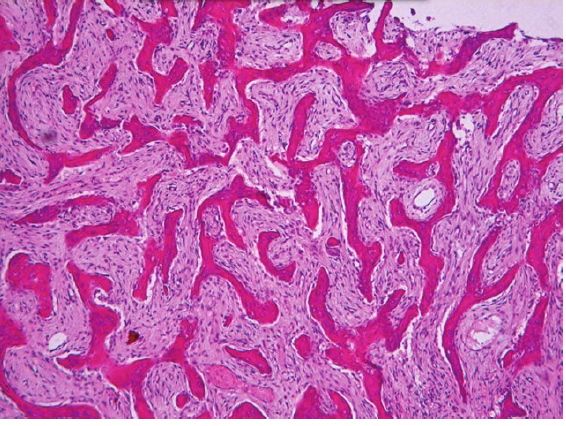

fibrous dysplasia histopathologic features

chinese letter appearance